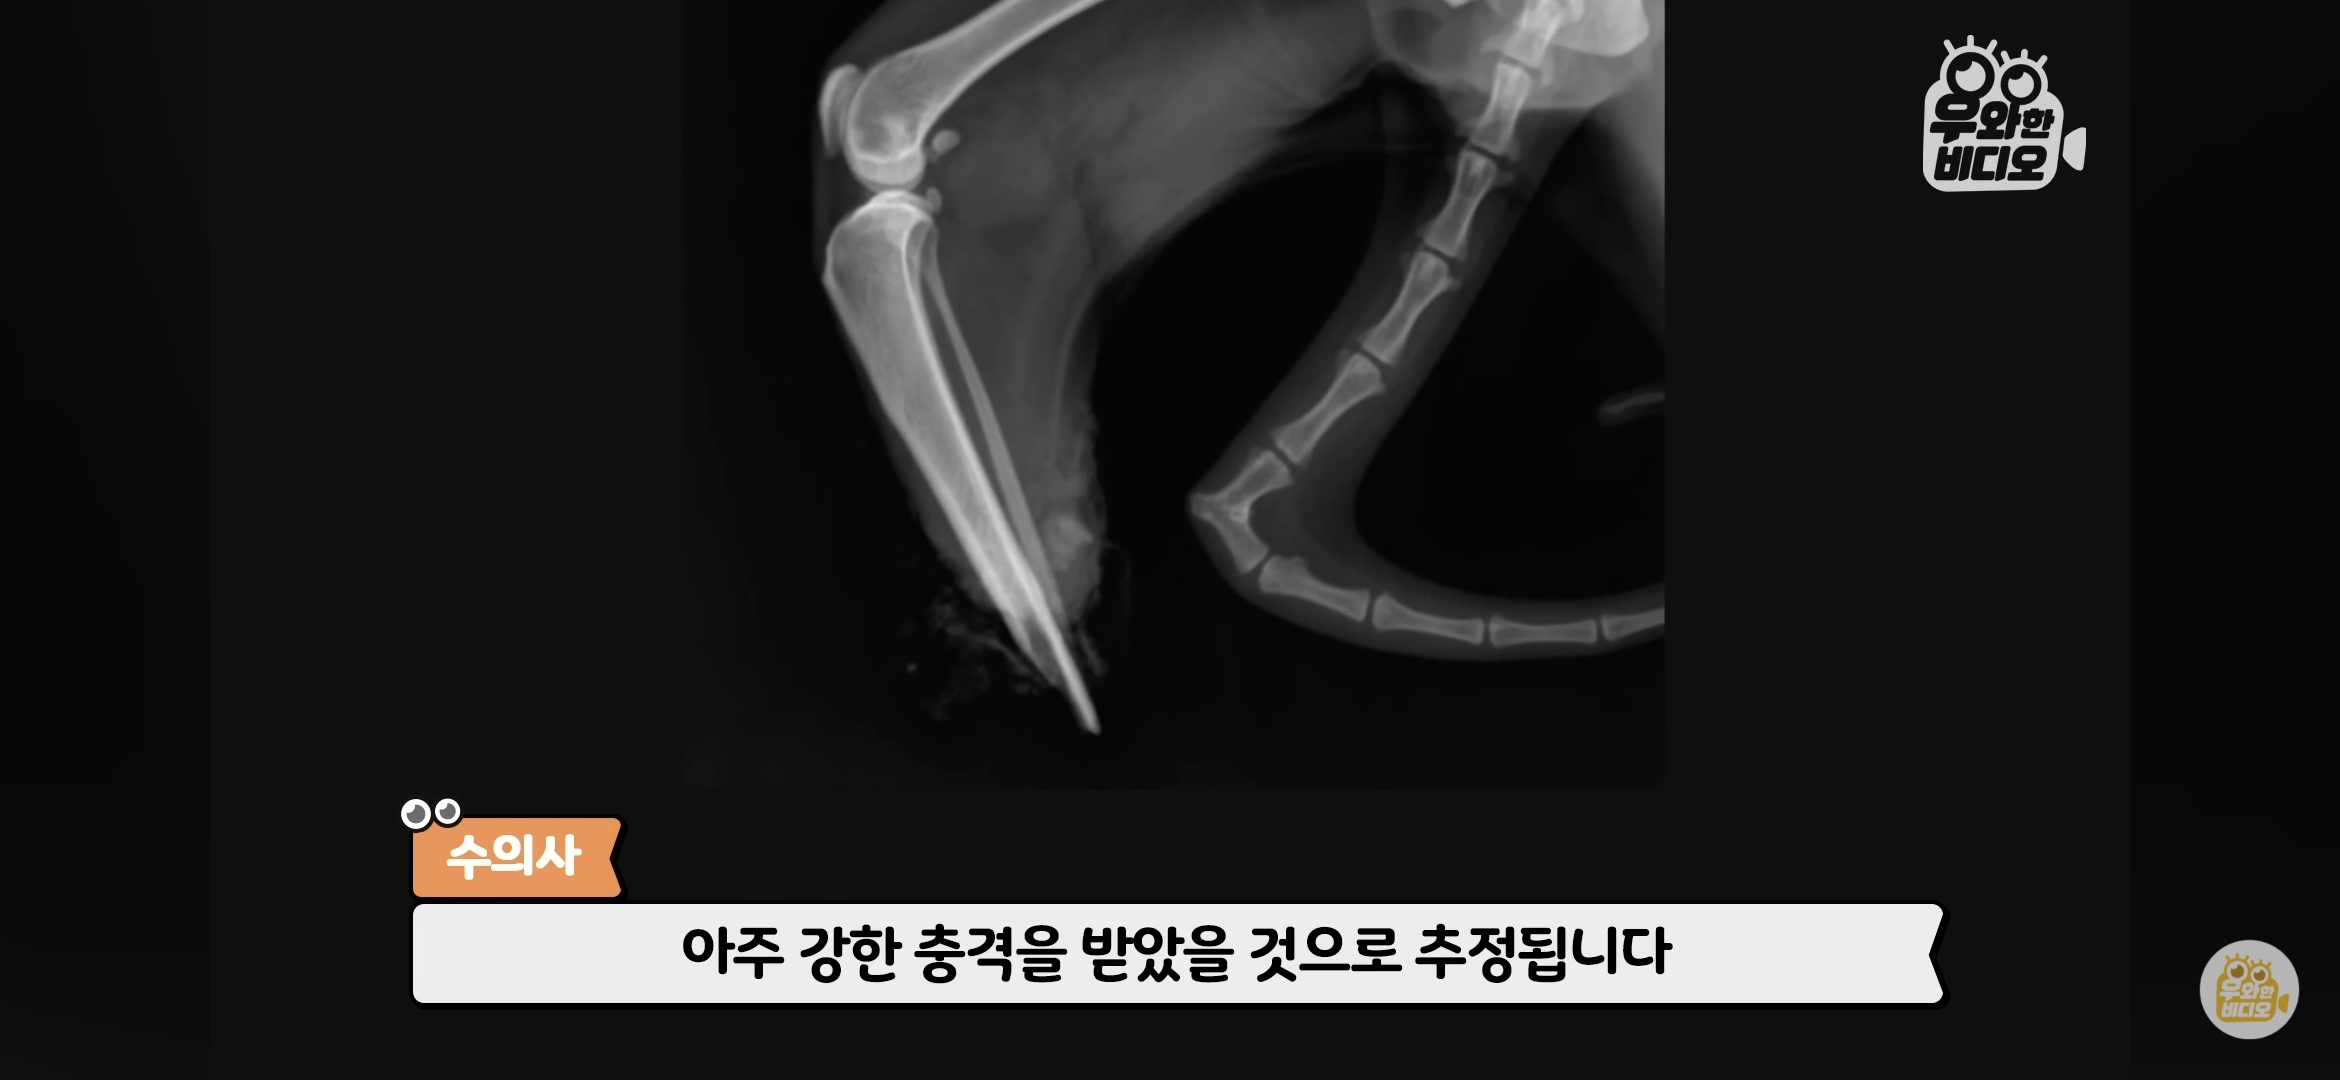

[눈물한방울]자신의 잘린 다리를 직접 물고 돌아온 고양이